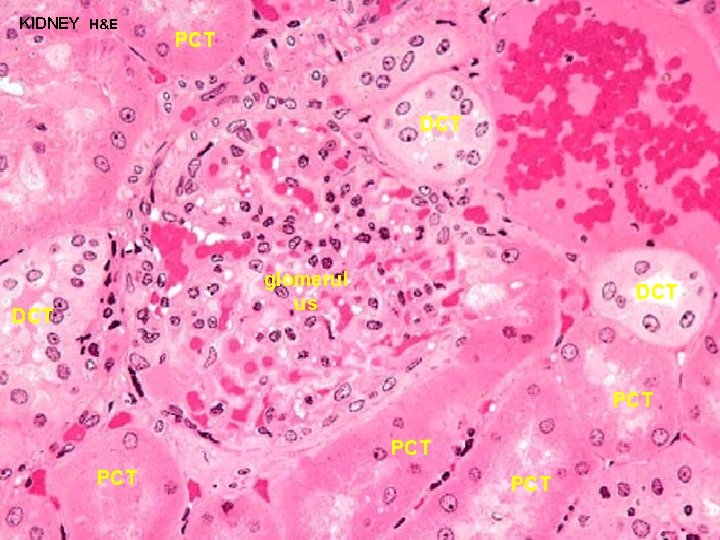

URINARY SYSTEM CORTEX: CORTICAL LABYRINTH 1 - RENAL CORPUSCLES 2 - PROXIMAL CONVOLUTED TUBULES - longer than DCT and thus more numerous - stain slightly darker and have a larger diameter than DCT - cells are larger and have an irregular luminal surface due to the presence of a “brush border” and glycocalyx 3 - DISTAL CONVOLUTED TUBULES - shorter than PCT and thus less prevalent - stain slightly lighter and have a smaller diameter than PCT - cells are smaller and cuboidal, thus more nuclei are apparent in a cross section of a DCT - luminal surface is more uniform since it lacks a brush border

URINARY SYSTEM CORTEX: CORTICAL LABYRINTH 1 - RENAL CORPUSCLES 2 - PROXIMAL CONVOLUTED TUBULES - 80 -90% of H 2 O and Na. Cl in glomerular filtrate is reabsorbed in addition to most organic materials: (glucose, proteins, amino acids, etc. ) CONVOLUTED 3 - DISTAL TUBULES - further resorption of H 2 O in presence of ADH - sodium resorption in response to aldosterone - calcium resorption in response to PTH

KIDNEY H&E DCT PCT PCT DCT PCT